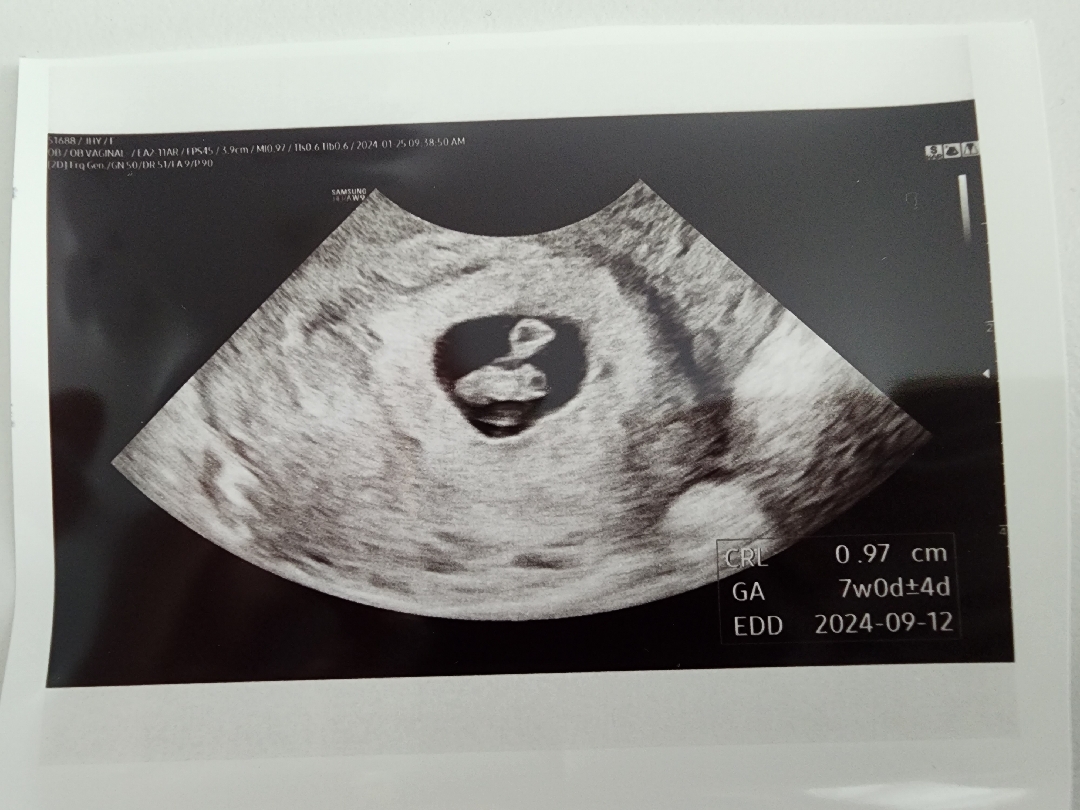

7주 0일 심장소리 듣고 왔어요.

처음 아기집하고 난황 확인했을때가 5주 0일이라고 하셨는데 2주 뒤에 갔더니 예정일이랑 주수 안변하고 딱 7주 0일이라고 하셨어요. 2주가 얼마나 길게 느껴지던지... 불안하기도 하고 악몽도 꾸고.. 걱정이 많았어요. 다행히 심장도 140으로 잘 뛰고 땅콩같은 아가도 보고나니 안심이 되더라고요. 또 2주 뒤에 오라고 하시는데 그때는 팔 다리 생겨서 젤리곰처럼 보일거라고^^ 심장도 160까지 뛰어야한다며... 남들 애기낳는거보면 금방 낳은 거 같았는데 ㅋㅋ 초기라 하루하루 하는 건 없이 기다리게 되네요 ㅋ